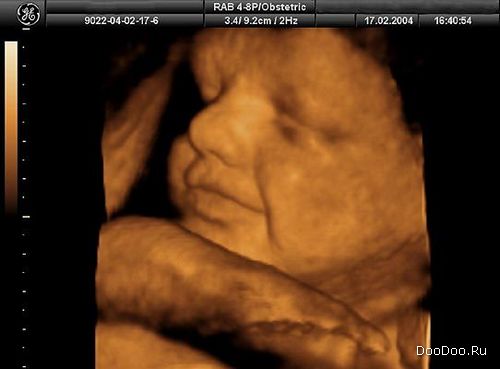

Ребенок теперь способен к движениям рук и пальцев. Может потереть щечку и носик. И силует ребенка виден немного лучше.

Передовая технология "4-D ультразвук" способна показать зародыша, сосущего свой большой палец, зевающего, улыбающегося и перемещающегося в режиме реального времени в матке.